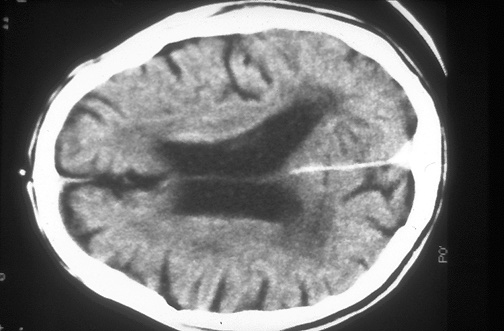

Image 5.1

This is a CT scan from another patient with the same disease. [Image contributed by Jeannette J. Townsend, MD, University of Utah]